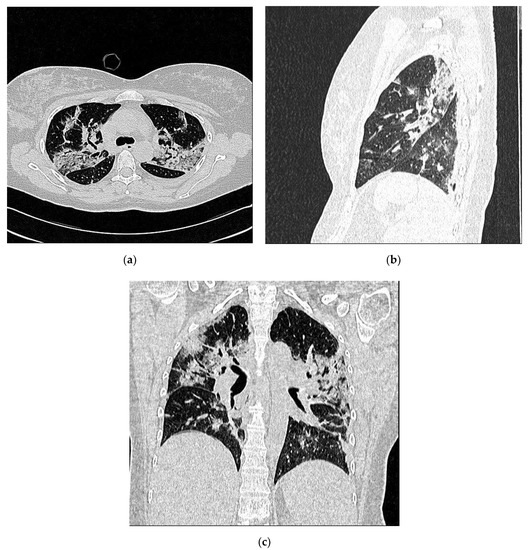

- Score 2:

- confluent B-lines which occupy >50% of the screen without irregularities pleural line. Score 2p: confluent B-lines with a clearly irregular pleural line (Figure 3).